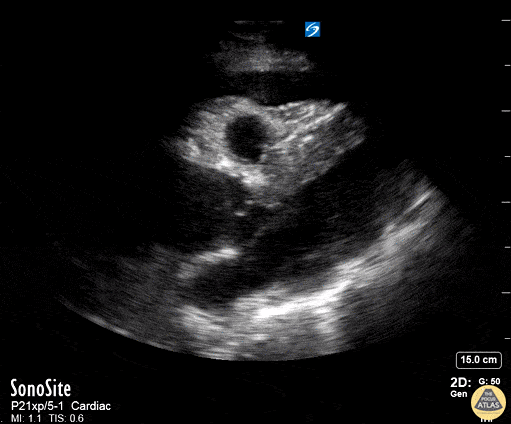

Pericardial Disease - Aortic Dissection with Tamponade - Parasternal Long

50 year old mandarin speaking man complains of vague central chest pain. You pursue a routine cardiac workup which is fairly normal. Upon discharging him, the nurse tells you his systolic in now in the 80's. You perform a RUSH exam - echo demonstrates a widened aortic outflow tract (well exceeding the rule of thirds) suggesting a Type A aortic dissection. You also see a pericardial effusion with right ventricular diastolic collapse. This is "the man jumping on the trampoline" or dimpling of the right ventricular free wall during diastole while it should be filling - clenching the diagnosis of tamponade. You better hope your CT surgeon is in house. Scroll to see the rest of the case for further images. Dr. Matthew Riscinti - Kings County Emergency Medicine, Dr. Benjamin Clearly - NYU Langone Emergency Medicine